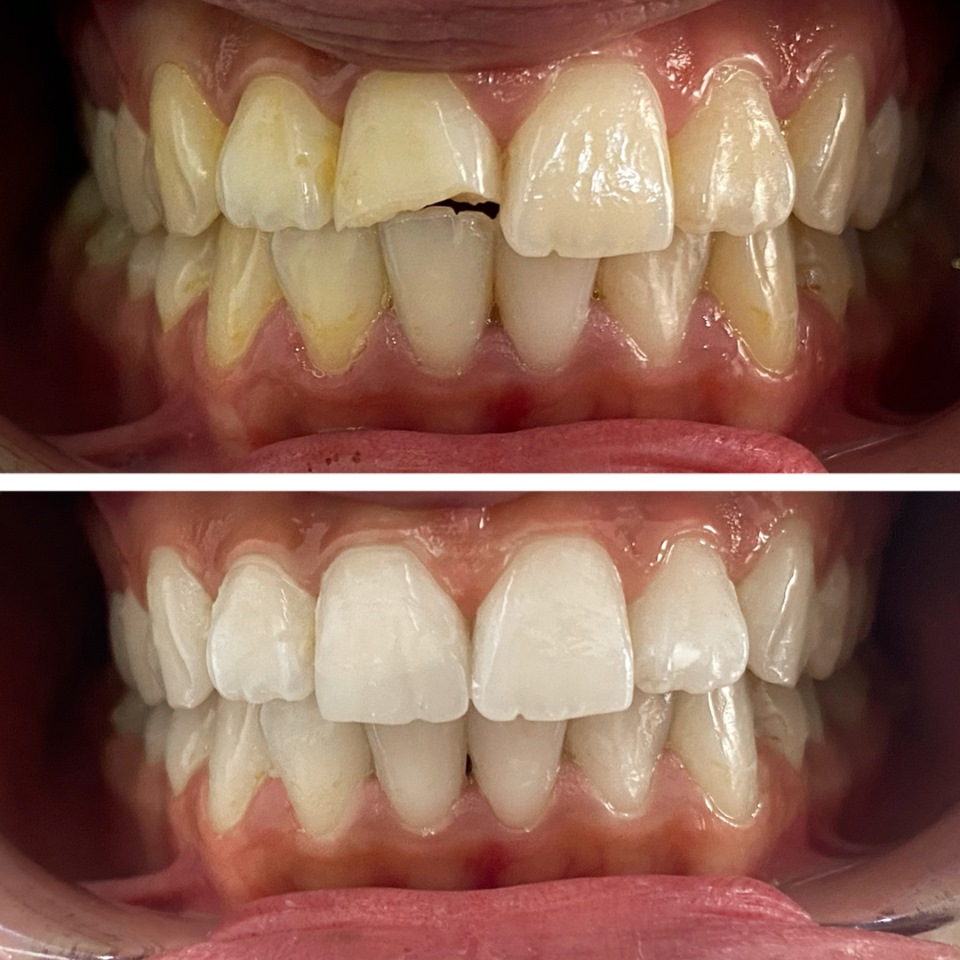

Smile Dental Clinic Turkey Gallery

Our Gallery and Happy Patients

Let’s make a change and put a perfect smile on your face with our dental clinic in Antalya/TURKEY.